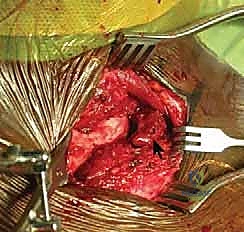

Dissection proceeds sharply through the subcutaneous tissue to the level of the platysma. The platysma is divided in line with the incision. Immediately deep to the platysma, the surgeon must be hyper-vigilant for the anterior jugular vein. This vessel is highly variable; if encountered, it should be carefully mobilized and retracted, or definitively ligated and divided to prevent massive hemorrhage during the deeper dissection. The medial fascia of the pectoralis major and the clavicular head of the sternocleidomastoid are identified. A subperiosteal dissection technique is strictly utilized to elevate these muscle attachments off the medial clavicle and the manubrium. Elevating full-thickness flaps preserves the vascularity of the bone and provides robust tissue for later closure.

Once the joint is exposed, the pathology is assessed. In an acute setting, the torn remnants of the anterior and posterior capsule are identified and tagged with heavy non-absorbable sutures. If the intra-articular disc is irreparably torn or blocking reduction, it may be excised, though preserving it is preferable if possible. Reduction of the joint is then performed under direct visualization. For a posterior dislocation, a bone hook or a robust towel clip is placed around the medial clavicle to pull it anteriorly and laterally, while an assistant applies lateral traction to the abducted arm.